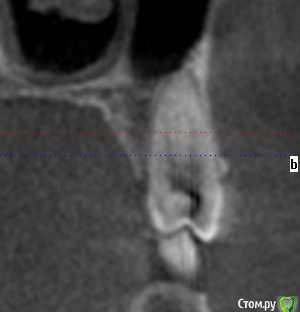

kozloff Опубликовано 15 ноября, 2015 Поделиться Опубликовано 15 ноября, 2015 Да, нужно исключить синусит.А еще можно заподозрить дисфункцию ВНЧС, на вашем снимке (ОПТГ) вызвает опасение расположение суставных головок. Но это может быть дефект снимка.Обязательно сделайте КТ, на одном снимке можно и пазухи рассмотреть, и ВНЧС. Ссылка на комментарий

kozloff Опубликовано 18 ноября, 2015 Поделиться Опубликовано 18 ноября, 2015 Подозреваю пульпит зуба 25И к лору не помешает сходить, есть отек слизистой. Гайморита нет. Ссылка на комментарий

Jurai Опубликовано 22 ноября, 2015 Поделиться Опубликовано 22 ноября, 2015 Есть проблема во фронтальном участке верхней челюсти: общая убыль костной ткани, ячеистая структура кости. смещение зубов так, что корни изогнулись, это значит, что либо резорбция (рассасывание) либо очень длительное уже идет воздействие. Могу подозревать новооборазование в этом участке.Вам нужна консультация челюстно-лицевого хирурга-онколога. 1 Ссылка на комментарий

janis1 Опубликовано 14 декабря, 2015 Автор Поделиться Опубликовано 14 декабря, 2015 Итак, продолжение моей эпопеи.Удалось попасть к челюстно-лицевому хирургу-онкологу раньше чем было запланировано. После очного осмотра и изучения КТ, профессор выдал заключение, что никаких проблем по его части он не нашел.После этого я был у терапевта, по поводу 25 -26 зубов, ничего кроме зубного камня на 26 зубе (кстати напомню я недавно делал гигиену ) он так-же ничего не нашел.На всякий случай сделали рентген зубов, даже как я понял с двух сторон, вот снимки: Ну и самое главное - проблема осталась, то-есть уже более двух месяцев я живу с болью в районе верхней челюсти...Что делать дальше не знаю...Очень надеюсь на вашу помощь! Ссылка на комментарий